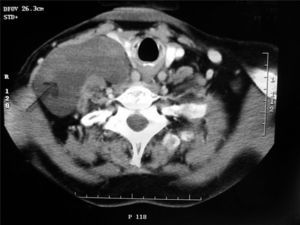

Presentamos el caso de una mujer de 77 años, sin alergias medicamentosas y con antecedentes de hipertensión arterial e intervención de prolapso uterino. Acude a nuestras consultas porque nota desde hace 6 meses un bulto indoloro en el cuello, de crecimiento lento pero constante. No cuenta disfonía, disnea ni disfagia. En la exploración se aprecia una tumoración en la región posterolateral del cuello, de unos 12 cm de diámetro, blanda, de compresión fácil, indolora y no pulsátil. La piel que lo recubre no muestra alteraciones y las cifras analíticas son normales, con marcadores negativos. Se realiza tomografía computarizada (TC) que informa de «tumor cervical multiloculado con contenido líquido, homogéneo, sin infiltrar estructuras vasculares ni musculares». El resultado de la punción aspirativa con aguja fina (PAAF) es compatible con linfangioma. Se intervino a la paciente bajo anestesia general y se realizó la exéresis total de la tumoración por cervicotomía externa, siguiendo el borde posterior del esternocleidomastoideo. El postoperatorio transcurrió sin incidencias y se le dio de alta al sexto día. El diagnóstico final anatomopatológico fue de linfangioma quístico.

Para el diagnóstico por imagen se utiliza la TC, que determina a la vez la extensión de la lesión y su relación con las estructuras circundantes (fig. 1); la resonancia magnética es menos usada y tiene gran rendimiento en los linfangiomas difusos2. La PAAF presenta alta sensibilidad para el diagnóstico, y en el caso descrito su resultado coincidió con el informe anatomopatológico definitivo. Tiene una exactitud del 85% en el estudio de masas cervicales malignas y hasta del 95% en masas cervicales benignas3. El diagnóstico de certeza nos lo da finalmente la histología de la pieza.